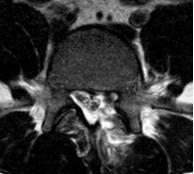

15岁的小王同学,在其母亲陈女士的陪同下来就诊。小王说,最近1月余来总感觉腰痛和左腿痛,一走路就加重,根本无法正常走路,呈跛行步态,陈女士见自己儿子小小年纪就这般难受,现在又是疫情期间,不知道如何是好,焦虑之际,经介绍,前来我院就诊,张昊主任医师予仔细、全面的查体,并阅读了相关影像学资料,经过团队的讨论,首先明确诊断为 “腰椎间盘突出症(L4/5 左侧)”。

针对该患者的诉求,张昊主任与其团队进行了反复的讨论并分析小王的问题,首先,小王才15岁,但腰椎间盘突出明确并伴有椎体后缘离断,神经受压明显,导致下肢疼痛、麻木,严重影响日常生活和学习,经过一段时间保守治疗,仍反复,并且越来越明显了,因此针对青少年的腰椎间盘突出症患者治疗方面该如何定夺呢?张昊主任分析,结合该患者的特殊性,又要考虑患者以后的影响,把相关治疗方案以及相应的风险等事宜详细告知陈女士,最终在微创理念下采用脊柱内镜下腰椎间盘摘除技术为小王进行手术,手术切口1cm,术后症状缓解,恢复良好,效果非常满意,第二天顺利出院。

术前影像